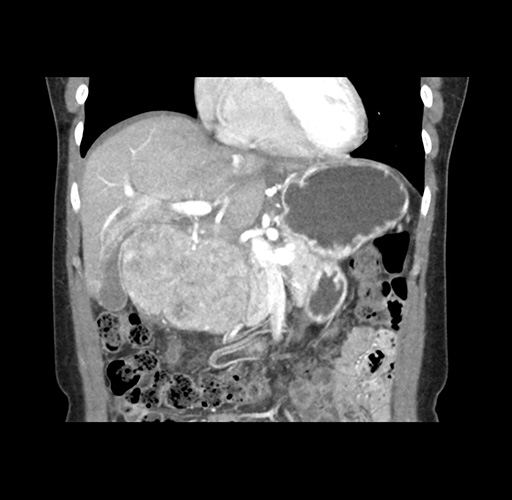

Left lateral sectionectomy [case 12]

Imaging Analysis

Look through the patient's CT scan to identify any areas of concern for the necessary procedure.

Based on your CT findings, which issue(s) would give reason for "planned slowing down moment(s)" in this case?

Considering a standard left lateral sectionectomy procedure, what step(s) of the operation would you do differently in this case ?